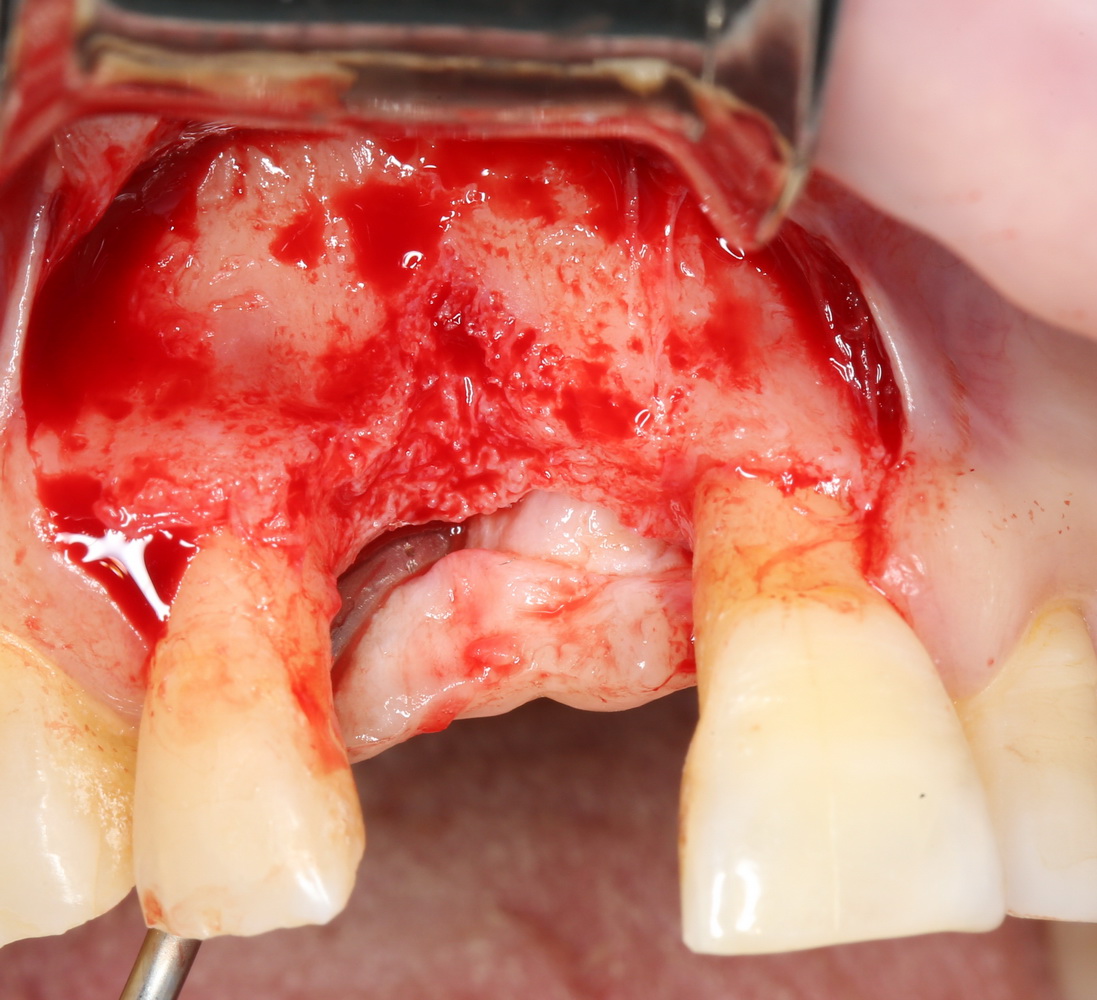

Другой вариант. Имплантируем, но существующего объема костной ткани недостаточно для получения адекватного эстетического и функционального результата:

Поэтому мы используем мембрану Geistlich BioGide и всё ту же аутокостную стружку:

Вот чем мне нравится мембрана BioGide — так это своими свойствами. Предсказуема до мелочей.

Во влажном состоянии она эластична и податлива, поэтому нет необходимости использовать пины или винты:

ну и, швы: